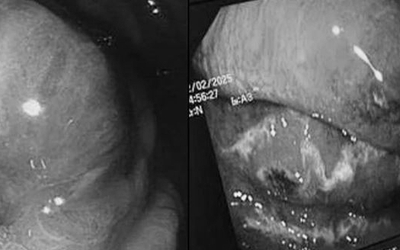

"Thủ phạm" khiến người đàn ông 68 tuổi nguy kịch, dạ dày và thực quản hoại tử nặng

Mới đây, Khoa Hồi sức truyền nhiễm (A4-D) – Viện Lâm sàng các Bệnh truyền nhiễm - Bệnh viện Trung ương Quân đội 108 đã tiếp nhận và điều trị thành công một trường hợp nhiễm khuẩn nguy kịch và rất hiếm gặp.